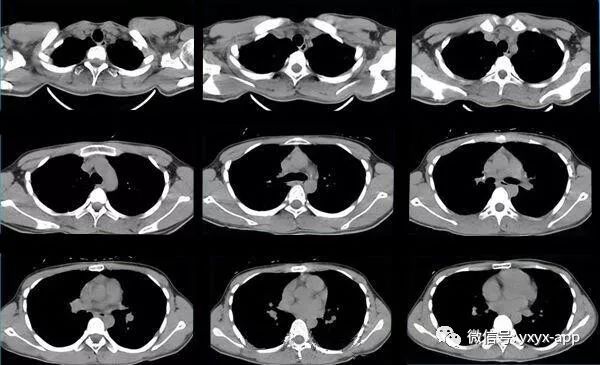

【现病史】半月前体检发现肺部阴影,行CT检查,抗炎后复查,无明显吸收、好转

10天后复查

评论:两肺斑片状磨玻璃影,与周围组织分界清楚,呈“地图样”表现,部分病变延伸至胸膜下,部分小叶间隔增厚,气管居中,肺门及纵膈未见肿大淋巴结影,未见胸腔积液。患者青年男性,临床症状轻微影像表现严重,抗炎治疗无效。考虑肺泡蛋白沉积症